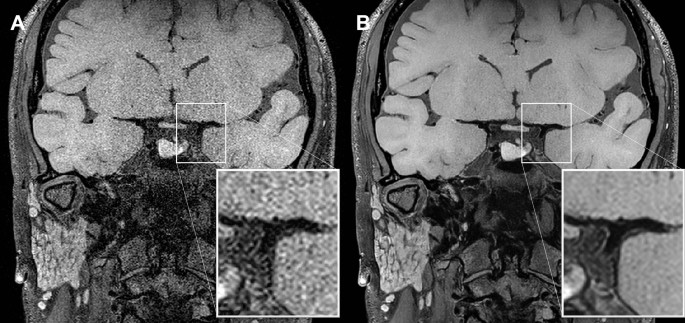

Vessel wall images were part of both training and validation datasets described above, and they are mutually exclusive from the dataset used during this study to maintain the study’s analytical validity. The trained model transforms conventional vessel wall images (Conv-VWI) into deep learning-augmented vessel wall images (DL-VWI) by performing super-resolution (0.28 × 0.28 × 0.45 mm3) and noise reduction (Fig. 1).

An example of DL-based image quality improvement on nonenhanced T1-weighted VWI. Conv-VWI (A) displays acceptable image quality and good wall-to-lumen contrast. DL-VWI (B) show excellent suppression of noise with well-preserved contrast. Especially, vessel walls are more clearly visualized on DL-VWI than on Conv-VWI (magnified views, bifurcation of internal carotid arteries).